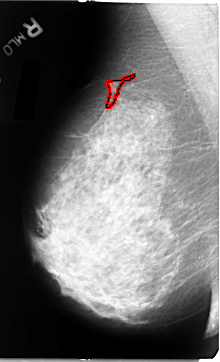

B_3078_1.RIGHT_MLO

FILE: B_3078_1.RIGHT_MLO.OVERLAY

TOTAL_ABNORMALITIES 1

ABNORMALITY 1

LESION_TYPE MASS SHAPE IRREGULAR-ARCHITECTURAL_DISTORTION MARGINS SPICULATED

ASSESSMENT 3

SUBTLETY 3

PATHOLOGY BENIGN

TOTAL_OUTLINES 1

BOUNDARY